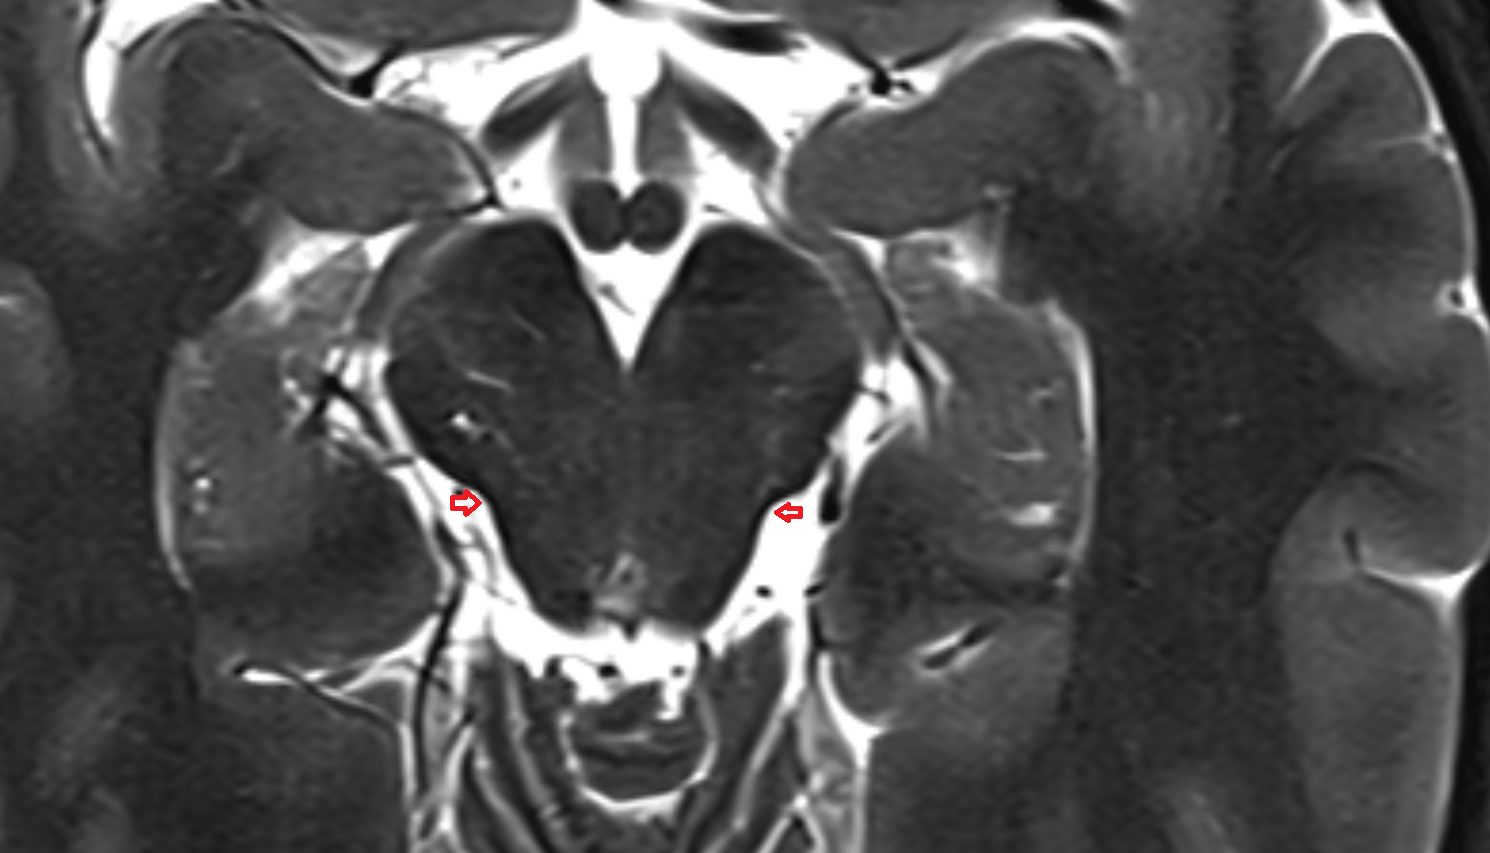

- Hippocampus